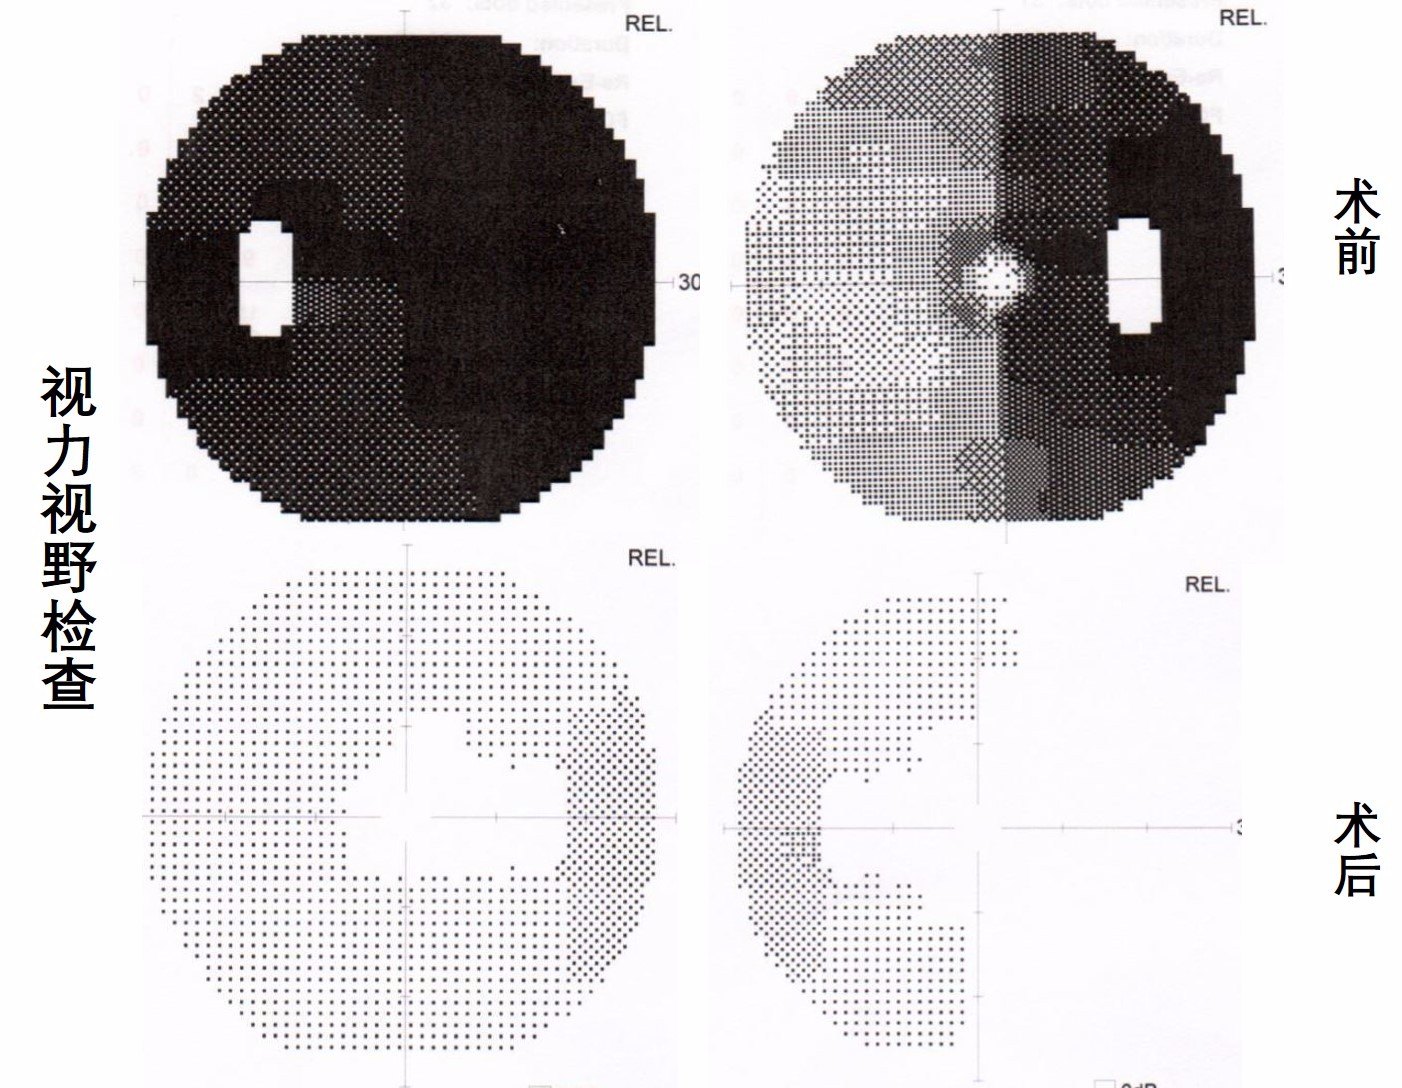

术后复查视力视野检查示:视野较术前明显改善。

术后患者恢复顺利,视野改善明显,视力无明显变化。患者精神状态较术前明显改善:“是医师帮我从黑暗中解脱出来,重见光明,感谢医生给我发现美的眼睛!”。